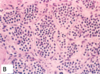

Smudge Cells

in [CLL-SLL]

[small lymphocytes w/scant cytoplasm]

see in a lymph node of [CLL-SLL]